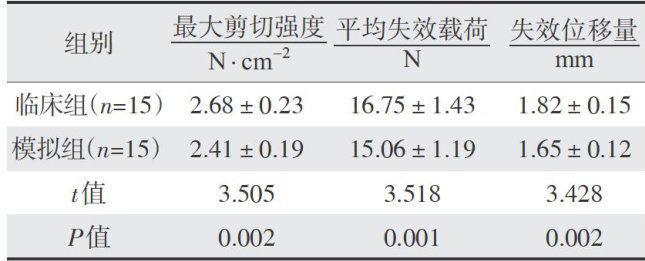

研究报告专论 | 铸瓷贴面粘接修复体护理策略对前牙美学完整性影响研究

研究报告专论 | 铸瓷贴面粘接修复体护理策略对前牙美学完整性影响研究